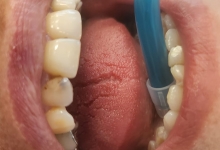

O igiena riguroasa a cavitatii bucale, presupune folosirea urmatoarelor:

– un periaj corect;

– ata dentara si apa de gura;

– periuta interdentara;

– folosirea dusului bucal.